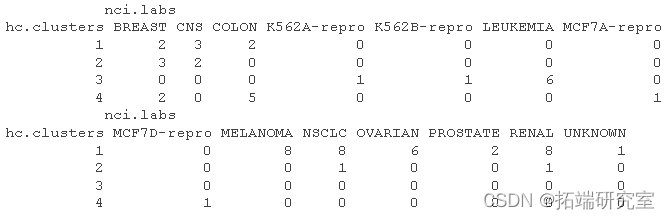

table(hrs,ncbs)

我们可以看到一个清晰的模式,即所有白血病细胞系都属于聚类 3,其中乳腺癌细胞分布在三个不同的聚类中。